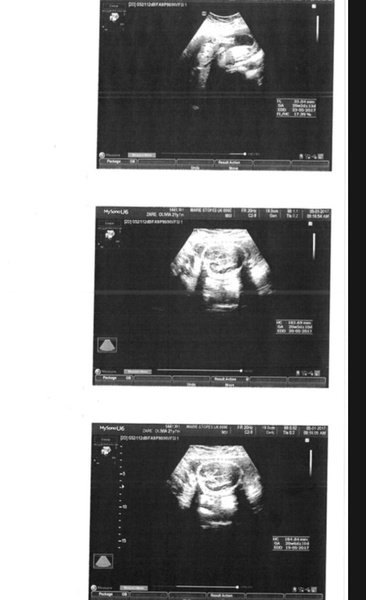

I just wondered if anyone can make out anything in my ultrasound images? I can't see for looking Confused

Looks like the top of the skull to me, can't see much else!

From what I can make out the bottom two look like head/brain and the top could be a leg? Odd scan photos to give you, they usually do a profile pic!

I think they've given you anatomical ones rather than the classic side profile. After lots and lots of brain scans I'd say bottom 2 are skull/brain. No idea about the top though